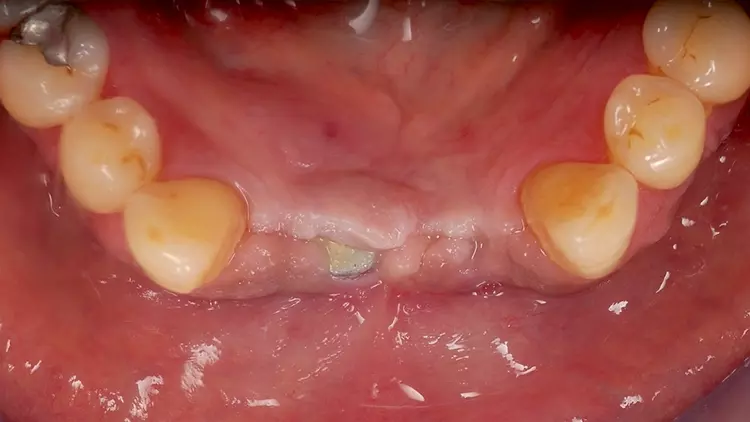

Als Interimsversorgung wurden herausnehmbare, klammerverankerte Prothesen aus Methylmethacrylat verwendet. Nach der dreimonatigen Einheilzeit erfolgten die Implantatfreilegung und die Versorgung mit Einheilkäppchen. Bei der Freilegung der Implantate und der Versorgung mit Einheilkäppchen sowie zum Zeitpunkt der Abformung mit den Abutments in situ lag eine reizlose klinische Situation ohne Anzeichen einer Entzündung im Implantatbereich vor (Abb. 4 und 5).

Der fehlende Zahn 24 wurde ebenfalls mittels eines Semados RS Implantats (BEGO Implant Systems GmbH & Co. KG) mit einer Länge/einem Durchmesser von 4,1/10,0 mm und einer monolithischen Zirkonoxidkrone ersetzt (3D Pro). Die klinische Situation konnte im Rahmen einer Nachuntersuchung im September 2022, fast zweieinhalb Jahre nach der Versorgung im Mai 2020 als sehr gut bezeichnet werden (Abb. 17-20).